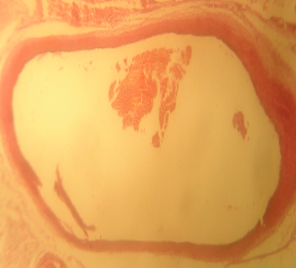

Morphological structure of aorta’s rats

Aorta’ slide was made every week for one month. Each group of the rats was killed, and the aorta’s rat was observed. From the morphological structure of aorta’s rat, atherosclerosis was scored as follows: on 4 point: 0, normal; 1, widening of elastic fibers with few foam cells; 2, fragmentation of elastic lamellae with numerous foam cells and fibrosis; 3, smooth muscle cells proliferation, medial lipid infiltration and fibrosis; 4, lipid-calcic plaque or ulcerated plaque [10].

Table 1: Distribution of aortic atherosclerosis scores at D90 in two groups of rat receiving atherogenic diet (n = 4)

| Lesions scores | A1 | A2 | A3 | A4 | B1 | B2 | B3 | B4 | C1 | C2 | C3 | C4 | D1 | D2 | D3 | D4 |

| 0 | - | - | 1 | 3 | - | - | - | 2 | - | - | - | - | 3 | 4 | 3 | 3 |

| 1 | 1 | 3 | 3 | 1 | 1 | 1 | 2 | 2 | 2 | - | - | - | - | - | 1 | 1 |

| 2 | 3 | 1 | - | - | 2 | 1 | 1 | - | - | 1 | 1 | 1 | - | - | - | - |

| 3 | - | - | - | - | 1 | 2 | 1 | - | 2 | 2 | 1 | 1 | - | - | - | - |

| 4 | - | - | - | - | - | - | - | - | 1 | 2 | 2 | - | - | - | - |

A1, A2, A3, A4 is morphological structure of aorta’s AND rats fed atherogenic diet for 2 mo and continuing with AND for 1 w, 2 w, 3 w and 4 w; B1, B2, B3, B4 is morphological structure of aorta’s atorvastatin rats fed atherogenic diet for 2 mo and continuing with atorvastatin for 1 w, 2 w, 3 w and 4 w; C1, C2, C3, C4 is morphological structure of aorta’s rats fed atherogenic diet for 9th week, 10th week, 11th week, 12th week; D1, D2, D3, D4 is morphological structure of aorta’s rats fed normal diet for 9th week, 10th week, 11th week, 12th week.

The rats (n=4) from each group were sacrificed every week to observe the morphological structure of the aortas. From the lesions, it showed that AND could help chance severity aortic atherosclerosis. The score varied from group A1 until group A4. The aorta morphology of group A1 showed that one aorta had a widening of elastic fibers with few foam cells (score 1) and three aortas had the proliferation of smooth muscle cells (score 3) (fig. 5 A1). AND administration for four weeks could repair aorta condition. Group A4’ aorta morphology showed that three aortas became normal (score 0) and one aorta still had a widening of the first interlamellar (score 1) (fig. 5 A4). Atorvastatin administration could also help changing the severity of aortic atherosclerosis. The score also varied from group B1 until group B4. The aorta morphology of group B1 showed that one aorta had a widening of elastic fibers with few foam cells (score 1), two aortas had fragmentation of elastic lamellae with numerous foam cells and fibrosis (score 2), and one aorta had the proliferation of smooth muscle cells (score 3) (fig. 5 B1). Atorvastatin administration for four weeks could improve aorta condition. Group B4’ aorta morphology showed that two aortas became normal (score 0) and two aortas still had a widening of the first interlamellar (score 1) (fig. 5 B4). Contrarily, the morphological structure of atherogenic rats was getting worse week by week.

Fig. 5: Morphological structure of aorta in albino Wistar male rats 40x. A1, A2, A3, A4 is morphological structure of aorta’s AND rats fed atherogenic diet for 2 mo and continuing with AND for 1 w, 2 w, 3 w and 4 w; B1, B2, B3, B4 is morphological structure of aorta’s atorvastatin rats fed atherogenic diet for 2 mo and continuing with atorvastatin for 1 w, 2 w, 3 w and 4 w; C1, C2, C3, C4 is morphological structure of aorta’s rats fed atherogenic diet for 9th week, 10th week, 11th week, 12th week; D1, D2, D3, D4 is morphological structure of aorta’s rats fed regular diet for 9th week, 10th week, 11th week, 12th week. Black circle (O) = score 1; green circle (O) = score 2; red circle (O) = score 3; blue circle (O) = score 4